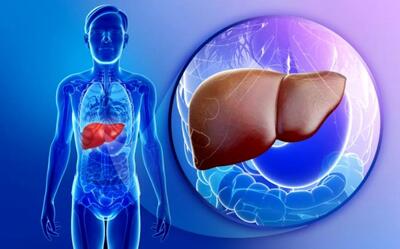

استامینوفن میتواند قاتل کبد باشد

استامینوفن زمانی که بهطور تجویز شده مورد استفاده قرار گیرد حتی برای افرادی که بیماریهای کبدی دارند نیز بیخطر است. با این حال مصرف بیش از حداین دارو بهصورت یکجا و یا استفاده زیاد و مداوم از آن در طول چند روز میتواند باعث مسمومیت کبدی شود.

مصرف بیش از حد استامینوفن برای کبد مضر است

کارشناس امور خدمات بستری و سرپایی سازمان غذا و دارو با هشدار نسبت به افزایش موارد مسمومیت ناشی از مصرف خودسرانه و بیش از حد مسکنها، بر ضرورت آگاهی و رعایت دوز مجاز داروها تأکید کرد.

هشدار درباره همهگیری خاموش کبد چرب

کبد چرب به یکی از بیماریهای شایع در میان مردم تبدیل شده و آمارهای رسمی نشان میدهند که ۴۰ تا ۵۰ درصد از افراد به درجاتی از این بیماری مبتلا هستند.